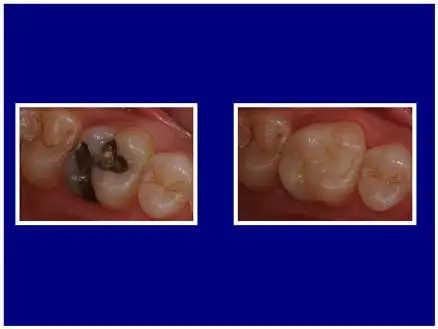

Here, we created a CEREC crown to restore an old, corroded silver filling on a tooth with significant dark stain and large cracks.